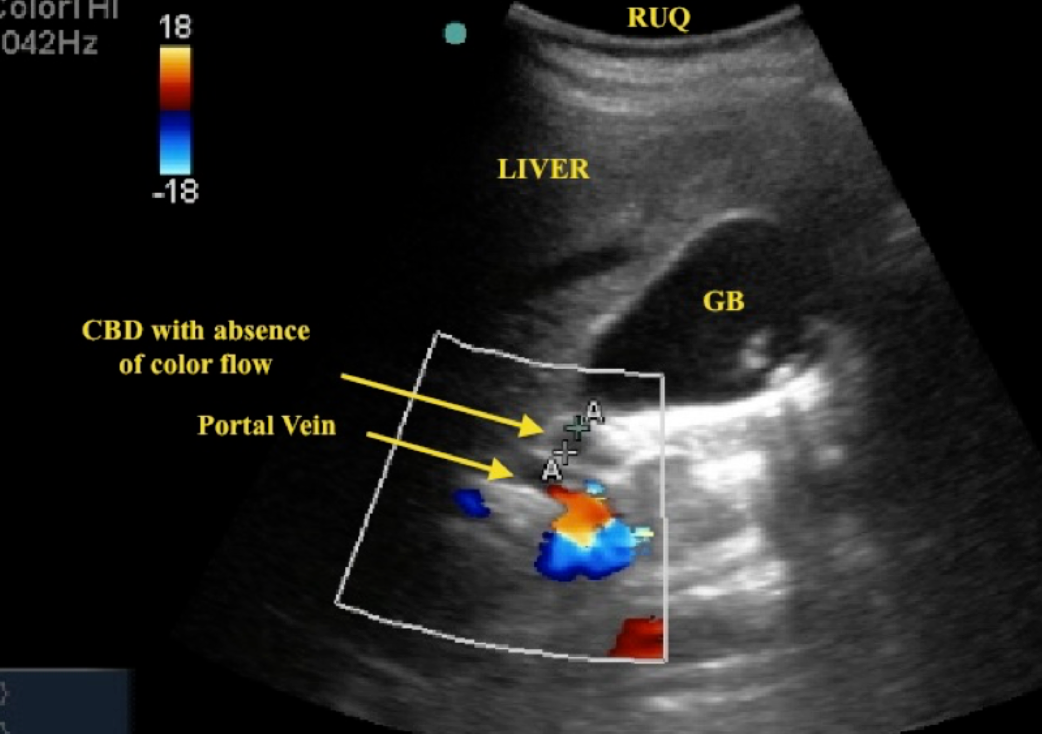

Dilatation of the intra- and extrahepatic biliary system can be identified at ultrasound, CT and MRI. #Z ***Ultrasound is usually the first test to be performed. ***

Dilated intrahepatic biliary ducts are seen at Ultrasound as serpentine structures paralleling the portal veins, a finding known as the âdouble channel signâ. Z

The common bile duct lies just in front of the portal vein and is dilated when more than 7 mm in diameter.

Dilated biliary ducts. - obstruction of biliary

(a) Longitudinal ultrasound scan showing a dilated common bile duct (CBD) measuring 11 mm in diameter lying in front of the portal vein (PV). Normally the duct is much smaller than the accompanying vein. A dilated intrahepatic duct is noted.